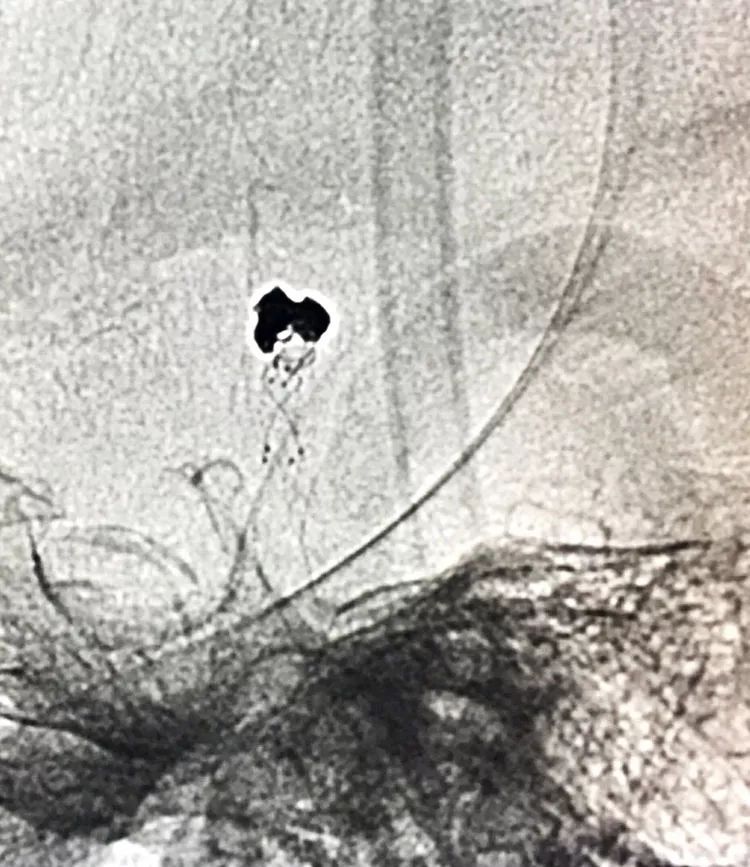

左椎动脉正位造影可以看到指向左方的子瘤。

左椎动脉工作位路图

先送入一段弹簧圈

将LVIS支架(3.5×15)跨瘤颈释放于右侧PCA-基底动脉内

在支架保护下输送弹簧圈栓塞瘤腔

此时从工作位(右斜17°反汤9°)看弹簧圈分布致密,微导管头已被顶到瘤颈处